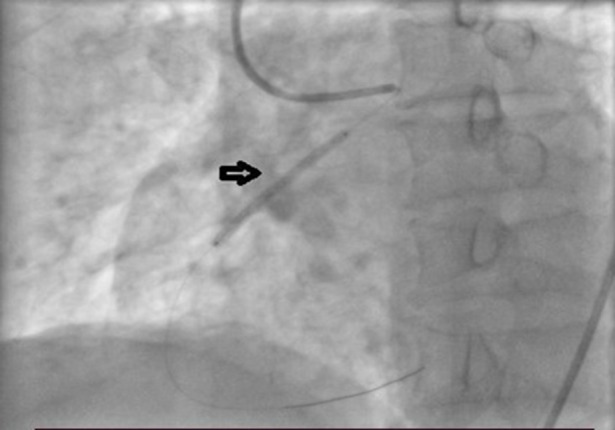

This case report examines a rare cardiovascular abnormality, the Aberrant Aortic Origin of the Right Coronary Artery (AAORCA), in a 75-year-old patient with a history of myocardial infarction, acute renal injury, and cardiogenic shock. Rapid medical intervention, including coronary angioplasty, demonstrated the significance of prompt care. Chronic issues, including tobacco use and left ventricular dysfunction, complicated matters, emphasizing the importance of comprehensive long- term therapy. This study underscores the critical clinical significance of AAORCA (Anomalous aortic origin of the right coronary artery) following the SCARE 2023 reporting criteria. This abstract emphasizes the delicate relationship between congenital defects, chronic hazards, and proactive healthcare in complex cardiovascular situations.